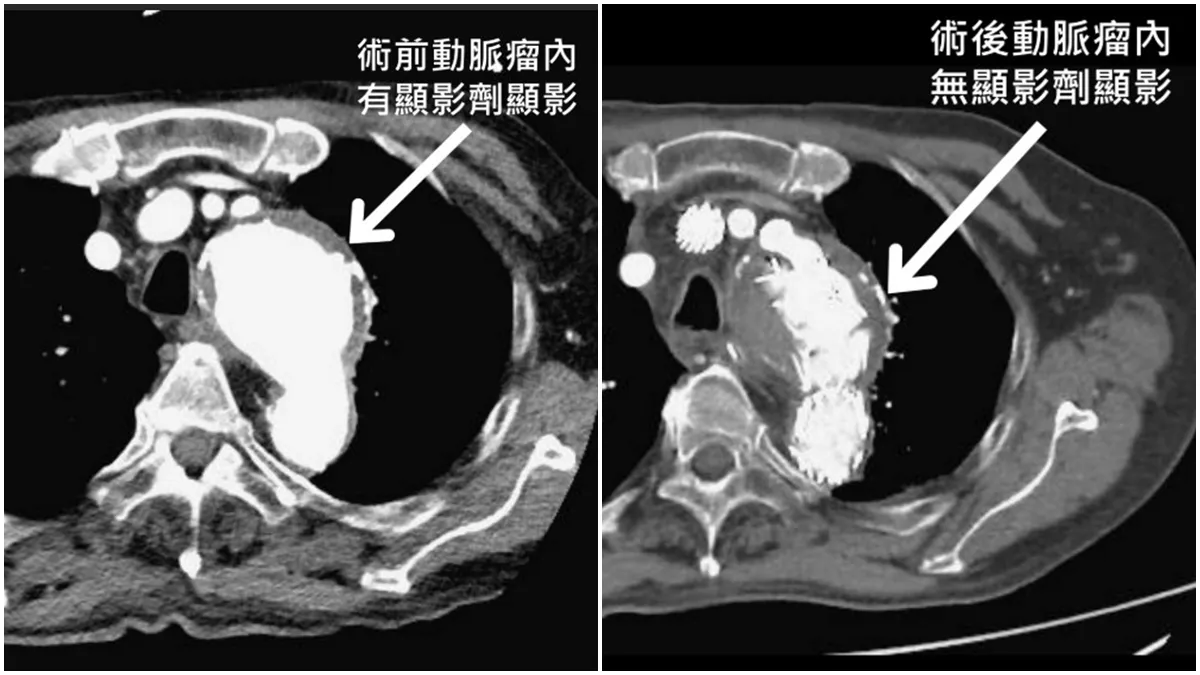

而最新的客製化胸主動脈開窗支架,則可依據每位患者獨特的主動脈形狀、走向、個別頸部分支動脈的大小、角度客製化設計。從鼠蹊部進入,在X光導引下置入適當位置,主動脈弓支架釋放後,再將三條較小的覆膜支架,分別置入頸部三條分支動脈,即可有效隔離動脈瘤預防破裂,並保持頸部血流暢通,降低中風風險。

跟傳統手術相比,客製化胸主動脈開窗支架手術僅針孔小傷口、約0.5公分,手術風險更低、術後恢復更快,住院期短,對高齡與高風險患者更安全,不過須自費約百萬元。北榮心臟外科團隊運用此技術,成功為80歲曾男與上述的謝先生治療複雜的主動脈弓部瘤,兩人術後恢復良好,也成為國內首二位以客製化胸主動脈開窗支架,完成全主動脈弓置換術的患者。